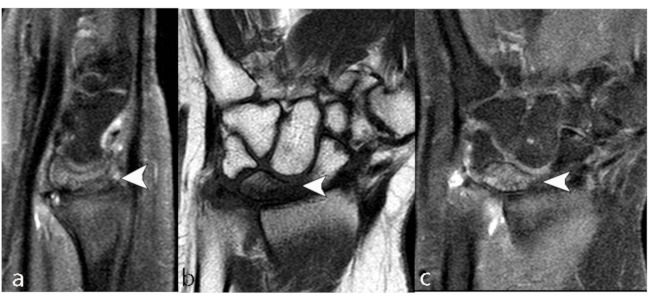

El hueso escafoides tiene grandes segmentos de cartílago hialino que cubre su superficie y, a causa de esto, las superficies externas no pueden ser penetradas por los vasos nutricios. El polo proximal del escafoides está predispuesto a NOA postraumática, debido a la ubicación distal de los principales vasos nutricios y el patrón retrógrado de suministro de sangre intraóseo.24,25

Las fracturas de la cintura se asocian a un 30% de incidencia de NOA, y las fracturas del polo proximal están asociadas a una incidencia cercana al 100%. La necrosis se desarrolla más temprano en pseudoartrosis proximales que en el resto.24

La RM nos permite diagnosticar la necrosis en estadios tempranos, así como documentar la vascularización del hueso escafoides antes y después del tratamiento en base a los cambios de señal. La baja intensidad de señal ponderada en T1 y en T2 en el polo proximal es muy sugestiva de necrosis avascular.

Se debe tener en cuenta a la enfermedad de Preiser, definida inicialmente como ON idiopática del hueso escafoides del carpo y posteriormente asumida como consecuencia de microtrauma, factores de riesgo vascular o medicamentosa (corticoides, hidroxicloroquina). Se manifiesta en dos tipos: